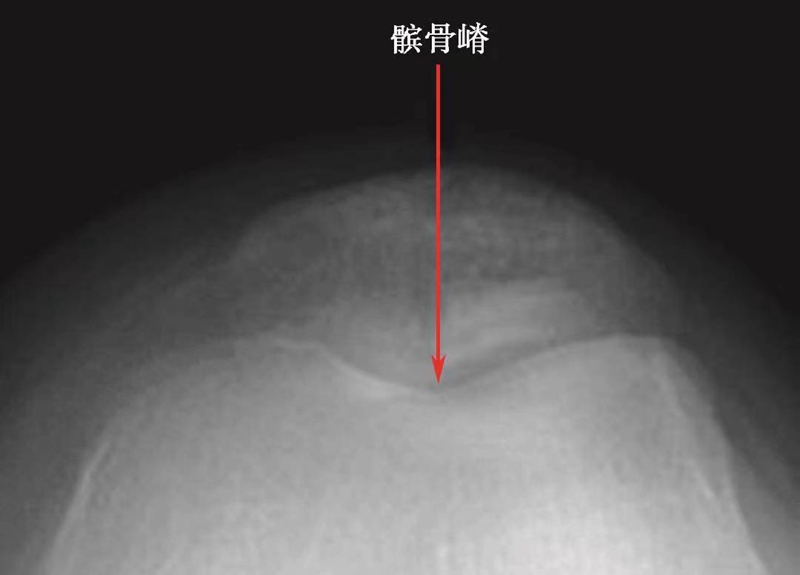

3 X线轴位像的髌骨形态

在髌骨轴位像上,髌骨的形态变化很大,Wiberg将髌骨形态分为3种类型(图9)。

WibergⅠ型(图10):髌骨内外侧关节面均为凹面,且内外侧关节面宽度基本一致,髌骨嵴位于中央,约占10%。此型是比较理想的髌骨形态。

图9 Wiberg分型示意图(红色箭头为WibergⅠ、Ⅱ、Ⅲ型的髌骨嵴所在位置)

图10 WibergⅠ型髌骨轴位X线片